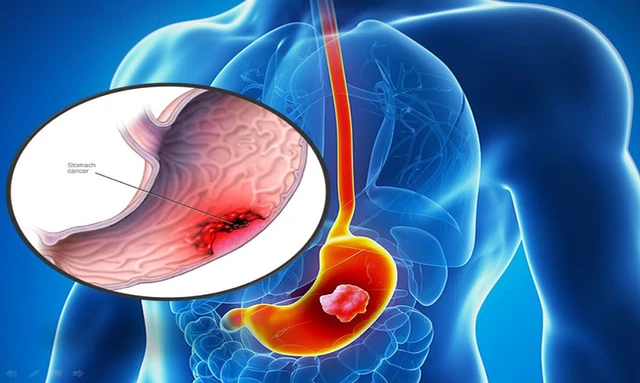

Các bệnh lý có thể hưởng lợi từ công nghệ xạ trị hiện đại trên hệ thống máy gia tốc Elekta Infinity

Xạ trị là phương pháp điều trị sử dụng các tia bức xạ năng lượng cao nhằm tiêu diệt tế bào ung thư. Theo số liệu của Cơ quan Năng lượng Nguyên tử Quốc tế ...